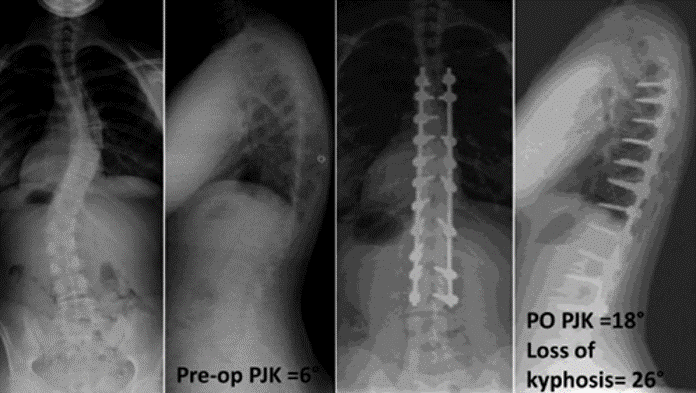

2)腰椎前凸(LL)过度矫正

图17 据文献报道,腰椎前凸(LL)过度矫正和SVA基线位置不当,均为增加PJK发生的风险因素